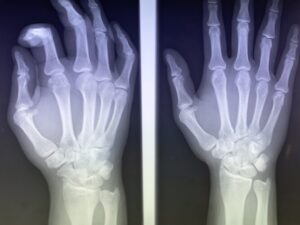

牛久市で指の怪我(突き指・骨折・脱臼)にお悩みの方へ:症状の見分け方から…